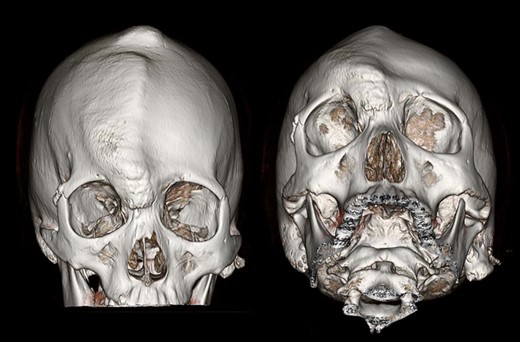

Three-dimensional CT of the patient’s skull. Protrusion of right frontal and parietal area was well observed.